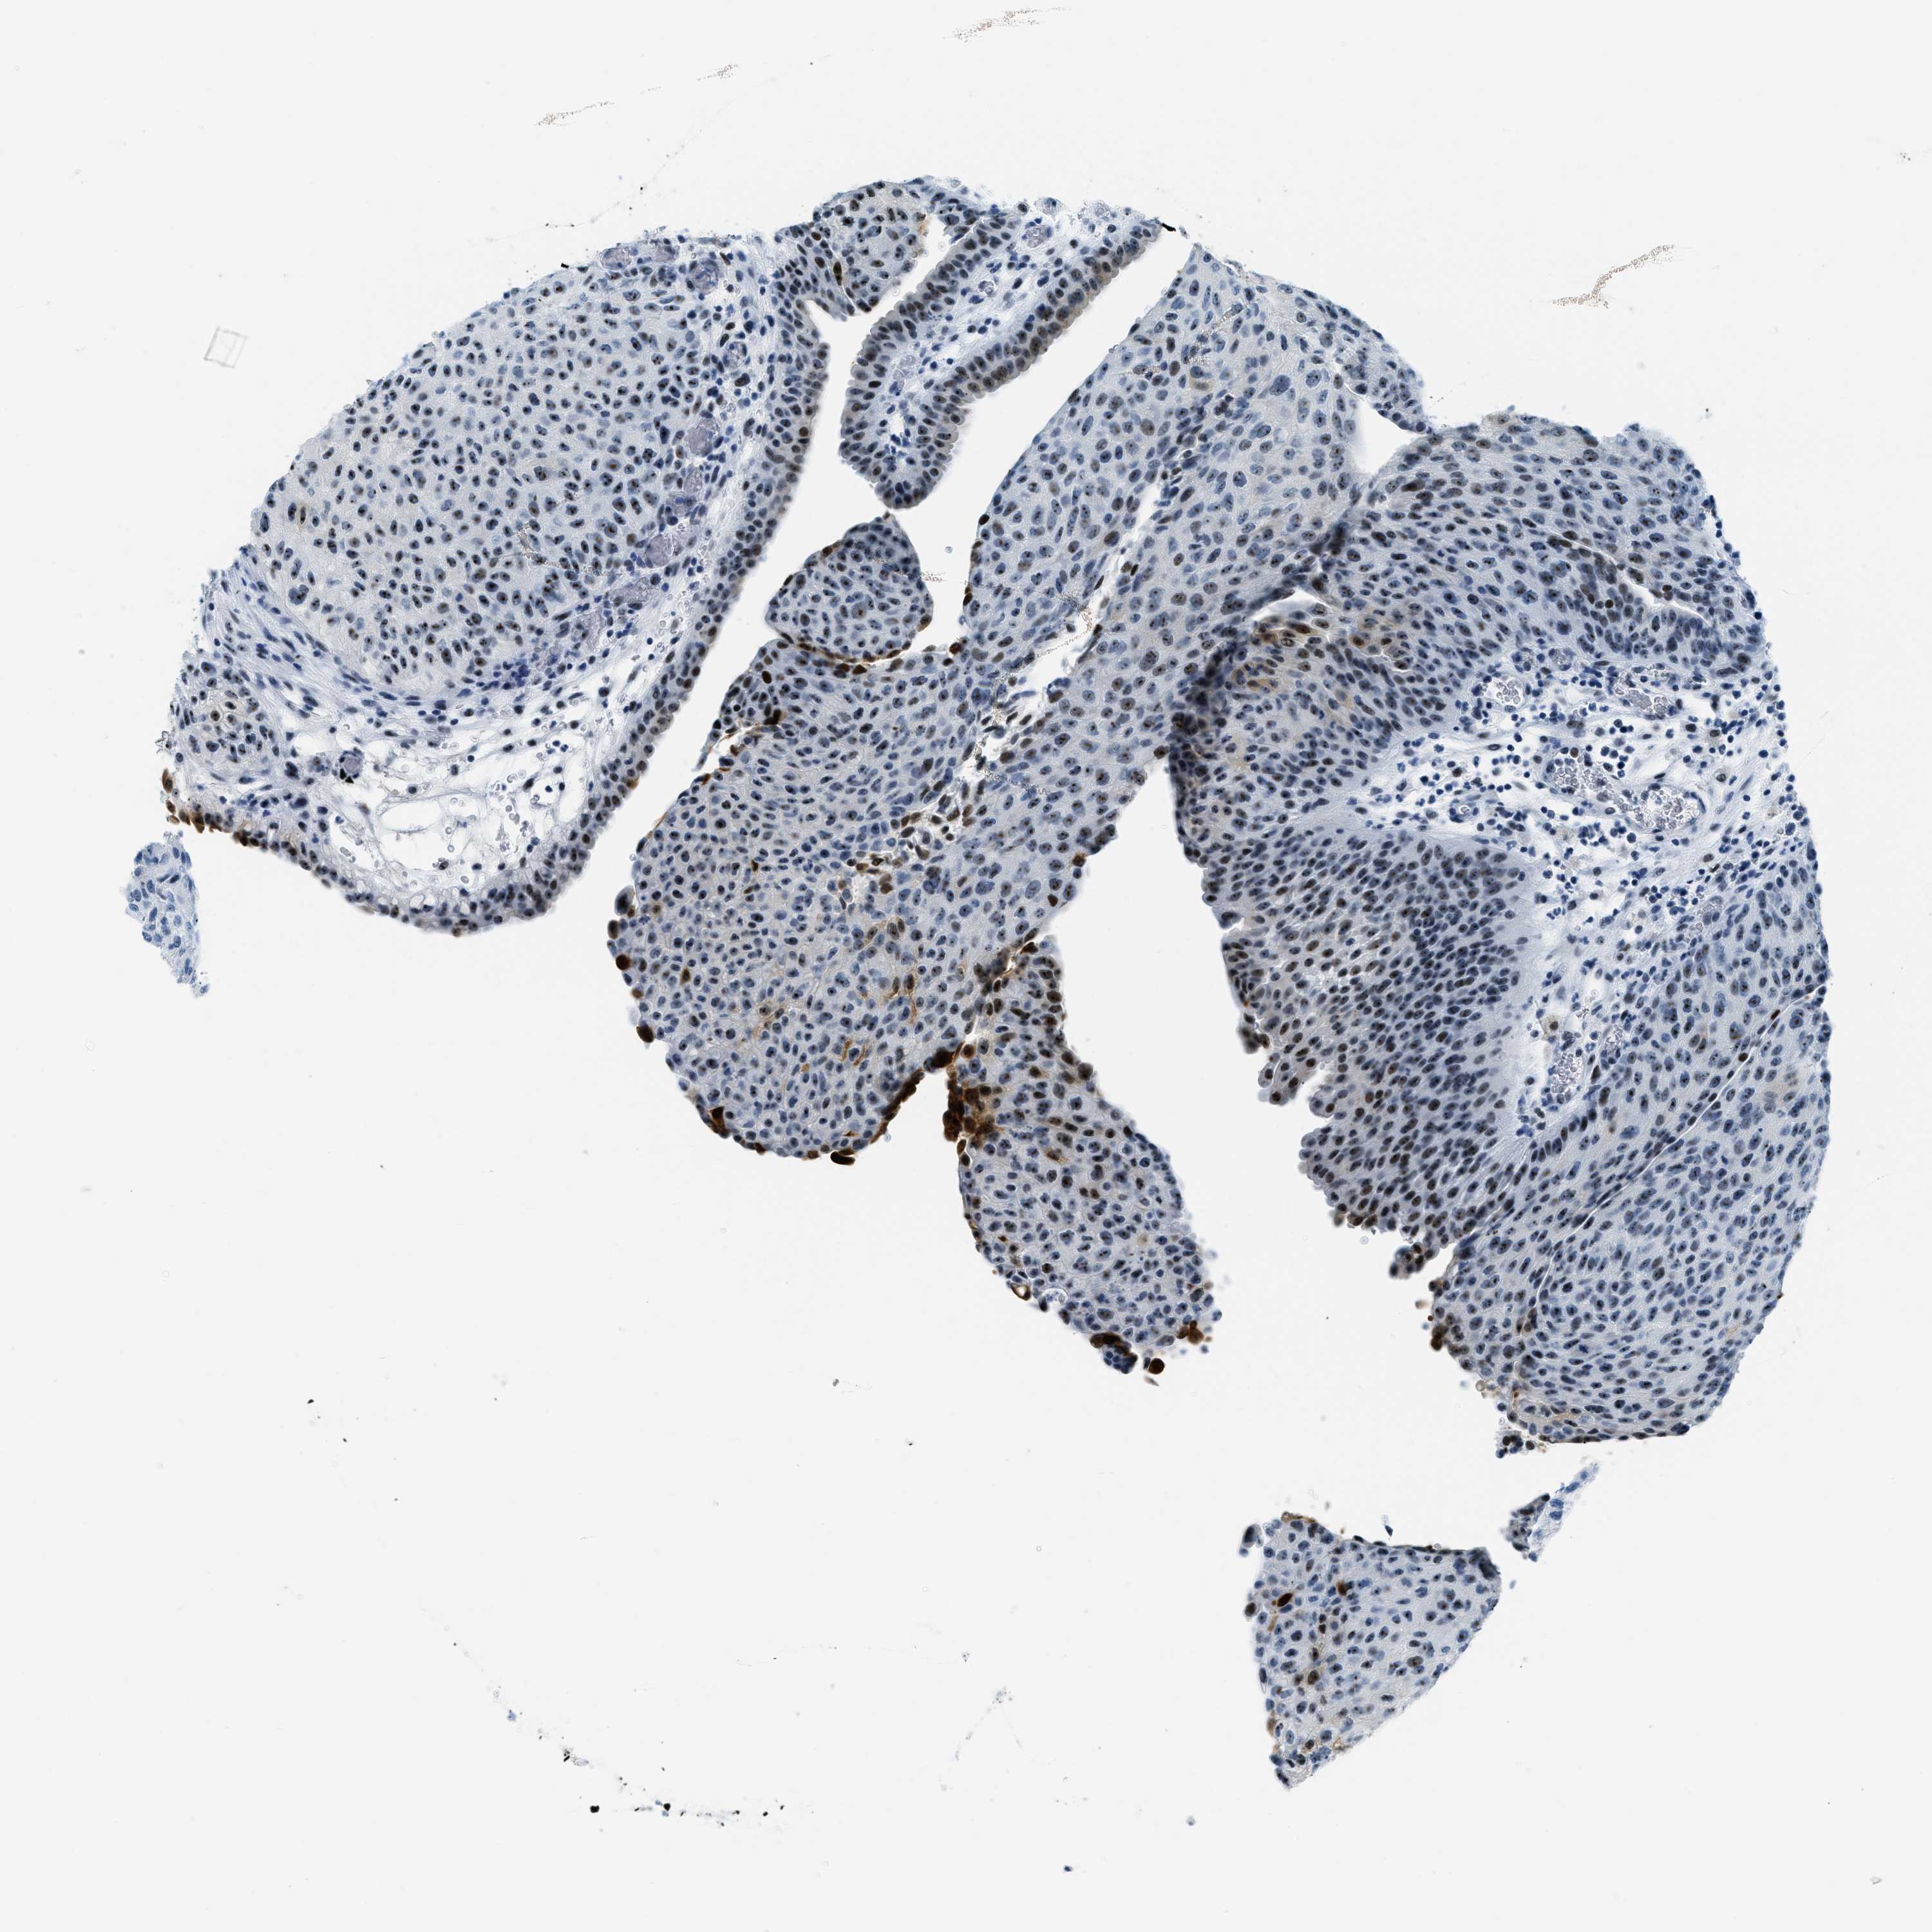

UROTHELIAL CANCER - Protein expressioni

A mouse-over function shows sample information and annotation data. Click on an image to view it in a full screen mode. Samples can be filtered based on level of antibody staining by selecting one or several of the following categories: high, medium, low and not detected. The assay and annotation is described here.

Note that samples used for immunohistochemistry by the Human Protein Atlas do not correspond to samples in the TCGA dataset.

Antibody stainingi

Antibody staining in the annotated cell types in the current human tissue is reported as not detected, low, medium, or high, based on conventional immunohistochemistry profiling in selected tissues. This score is based on the combination of the staining intensity and fraction of stained cells.

Each image is clickable and will lead to virtual microscopy that enables deeper exploration of all samples and also displays staining intensity scores, fraction scores and subcellular localization as well as patient and tissue information for each sample.

Antibody HPA015236

Staining

High

Medium

Low

Not detected

Intensity

Strong

Moderate

Weak

Negative

Quantity

>75%

75%-25%

<25%

None

Location

Urothelial carcinoma, Low grade

Urothelial carcinoma, High grade